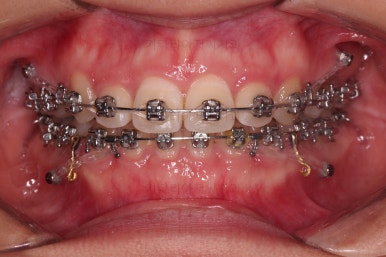

처음보다 입매도 많이 좋아졌지만 환자분은 기왕 하는김에 되는데까지 맥시멈으로 많이 입을 넣어보고 싶다고 하시더라고요.

원하시는 목표량은 이 뽑은 자리로 앞니를 다 넣어도 안될 듯 하여 추가로 사랑니 발치를 하고 미니스크류를 이용해서 더 넣어보기로 했어요.

위아래 좌우 모두 사랑니도 발치를 하고 네 군데 모두 미니스크류를 하여 최대한 당겨보기로 하였습니다.

이 쯤 되면 좋은 듯 한데, 그래도 아쉬운가 봅니다.

그래서 사직동교정치과 더 넣어보기로 했어요.

아무래도 입술이 두툼하신터라 표시가 그렇게 많이 안나는 점이 아쉬웠나 봐요.

치열이 매우 바르게 되었고 교합도 양호하며 뻗쳐 있던 앞니 각도도 좋아졌네요.

돌출의 느낌도 처음보다 많이 좋아졌어요.

웃을 때 보이는 치열의 느낌도 좋고요.